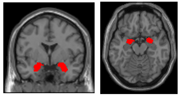

腹外側前頭前野

大脳半球外側面の前方部に位置する領域で、意思決定や情動など重要な機能に関与している(右図の赤い部分)。 元の記事へ